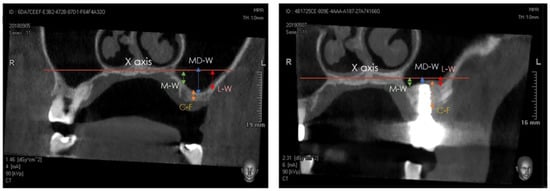

2.4. Tomographic Examination

- (a)

- medial sinus floor level (M-W);

- (b)

- middle sinus floor level (MD-W);

- (c)

- lateral sinus floor level (L-W).

3.4. Cone-Beam Computed Tomography Assessment

| Timepoints | Bone Crest Height (C–F) (mm) ± SD |

|---|---|

| T0 | 4.6 b ± 2.0 |

| T2 | 12.1 a ± 1.4 |

| Sinus Floor Level at Medial Aspect (M-W) (mm) ± SD | Sinus Floor Level at Middle Aspect (MD-W) (mm) ± SD | Sinus Floor Level at Lateral Aspect (L-W) (mm) ± SD | |

|---|---|---|---|

| T1 | 1.9 a ± 2.4 | −0.1 b ± 2.7 | 3.1 a ± 3.0 |

| T2 | 1.7 a ± 2.6 | 0.7 a ± 2.4 | 3.1 a ± 3.0 |